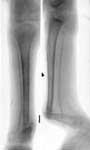

1.Врожденный ложный сустав костей левой голени.

2.Остеосинтез аппаратом Илизарова с одновременным удлинением голени.

3.Больной в аппарате Илизарова.

4.Результат лечения.